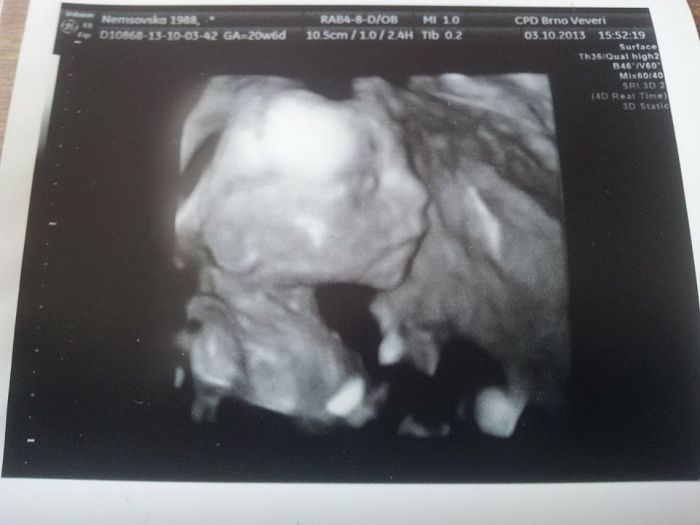

Vlasti, ja myslela, ze uz cekas 4 dite?? Vetsinou vsude pisou, ze kdyz uz jsi rodila citis pohyby driv, uz nekdy 18tt... A uz jsi to parkrat prosla a prozila :-) by jsi nam mela davat skoleni :-) :-) :-) jinak ja jsem 22tt a citim nekdy pohyby vic a nekdy treba cely den nic, nebo jenom malinko... Je to ruzny... Malej ma pul kila dle utz. Mozna to je i o stavbe tela, jsem vysoka a silnejsi takze se to proste ztraci, asi. Uz jsem objednana na 3D a na ten se tesim nejvic :-) jak ho uvidim... :-) smudlinek nas malej... Furt si rikam, komu bude podobnej...